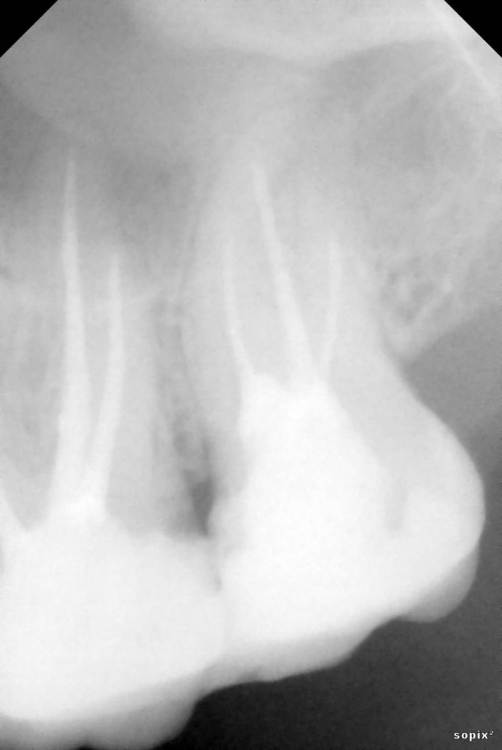

Siegfrid Опубликовано 29 июля, 2021 Поделиться Опубликовано 29 июля, 2021 Был у нескольких врачей в разных клиниках и мнения разошлись. В двух клиниках нашли проблемы сумма оказалась большой сходил в недорогую клинику, там проблемы не видят.. 2.6 и 2.7 Зуб со свищем 2 разных врача берутся лечить с шансом примерно 40% на успех, 1 врач говорит что только удаление. Ссылка на комментарий

Siegfrid Опубликовано 30 июля, 2021 Автор Поделиться Опубликовано 30 июля, 2021 Между зубами 2.6 и 2.7 набивается еда и гниет, когда я пошел в клинику на консультацию когда сделали снимок нашли что также плохо полечены каналы и для полного лечения двух зубов оказалась большая сумма которой у меня нету, я об этом сказал тогда мне предложили перепломбировать чтобы не набивалась еда, предупредив что непролеченные каналы со временем приведут к потере зубов. Я сходил в другую клинику, врач нашел кариес на одном из этих зубов но так как уходил в отпуск записал к другому врачу этого же заведения, я дожался своей очереди и вот он не видит проблем с зубами кроме того что со свищем. Что мне делать дальше? Ссылка на комментарий

St. Опубликовано 30 июля, 2021 Поделиться Опубликовано 30 июля, 2021 Добрый день. В верхних зубах есть большие пломбы с кариесом между зубами. Нужно покрыть их коронками, предварительно перелечив каналы. Если финансово пока не готовы к этому, то возможно временно откорректировать пломбы или сделать временные пластмассовые коронки. С нижним зубом рекомендации такие же - перелечить каналы и покрыть коронкой 1 Ссылка на комментарий